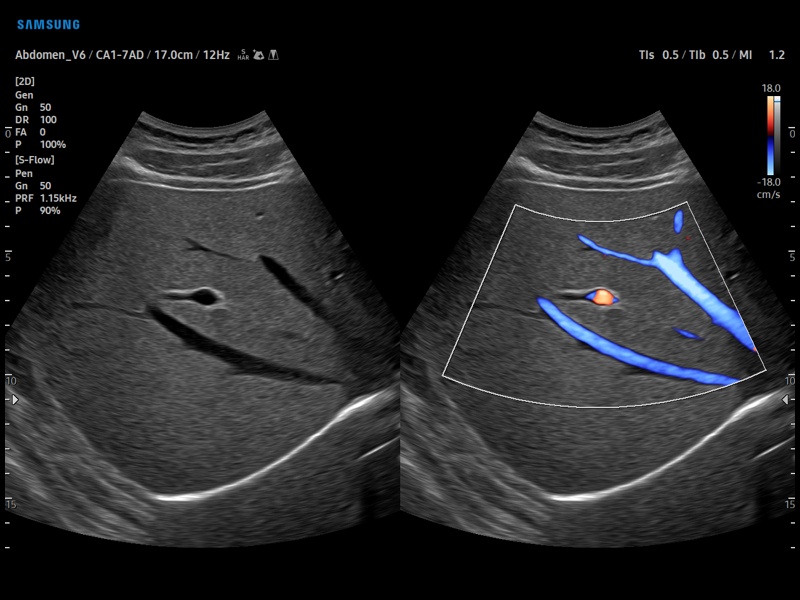

Особенности и диагностика левостороннего кровотока

.jpg)